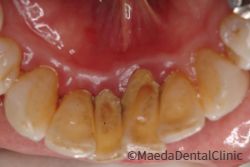

歯石

歯の裏側は歯石が付着しやすく、放置すると歯周病が進行してしまいます。